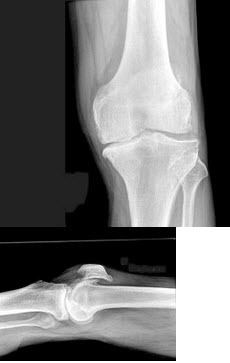

13、单项选择题

男,76岁,长久站立时左膝关节疼痛,可扪及捏发音,结合图像,最可能的诊断是()